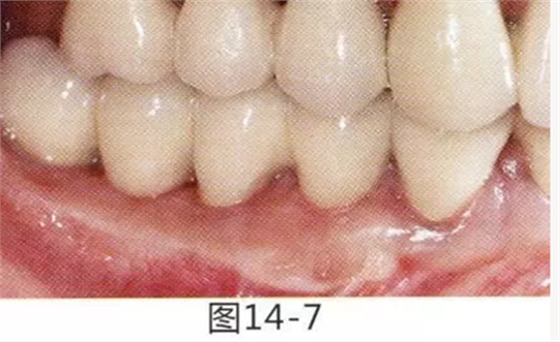

有3~4mm牙周袋并且沒有附著齦的存在,系帶也在牙頸部附近位置的病例。通過FGG(游離齦移植)獲得附著齦同時切除系帶后,即使經(jīng)過了很長時間,牙齦邊緣依然保持安定的狀態(tài)。

圖16-1 右3,4牙周袋探診值為3~4mm,基本沒有附著齦。右下3部位的系帶也附著在牙頸部附近,由于清潔困難而引發(fā)了炎癥。

圖16-2 由于磨牙部缺失,為了能夠進行固定修復(fù)而在右下6位置植入種植體,制作右下3,4,5,6固定橋冠。為了增加基牙右下3,4周圍的附著齦,在實施FGG同時去除系帶。

圖16-3 獲得了足夠附著齦,可以抵抗刷牙等外部刺激。

圖16-4 獲得充分附著齦,易清潔的狀態(tài)。修復(fù)體之間的鼓形間隙大小均一也使清潔性得到提升。